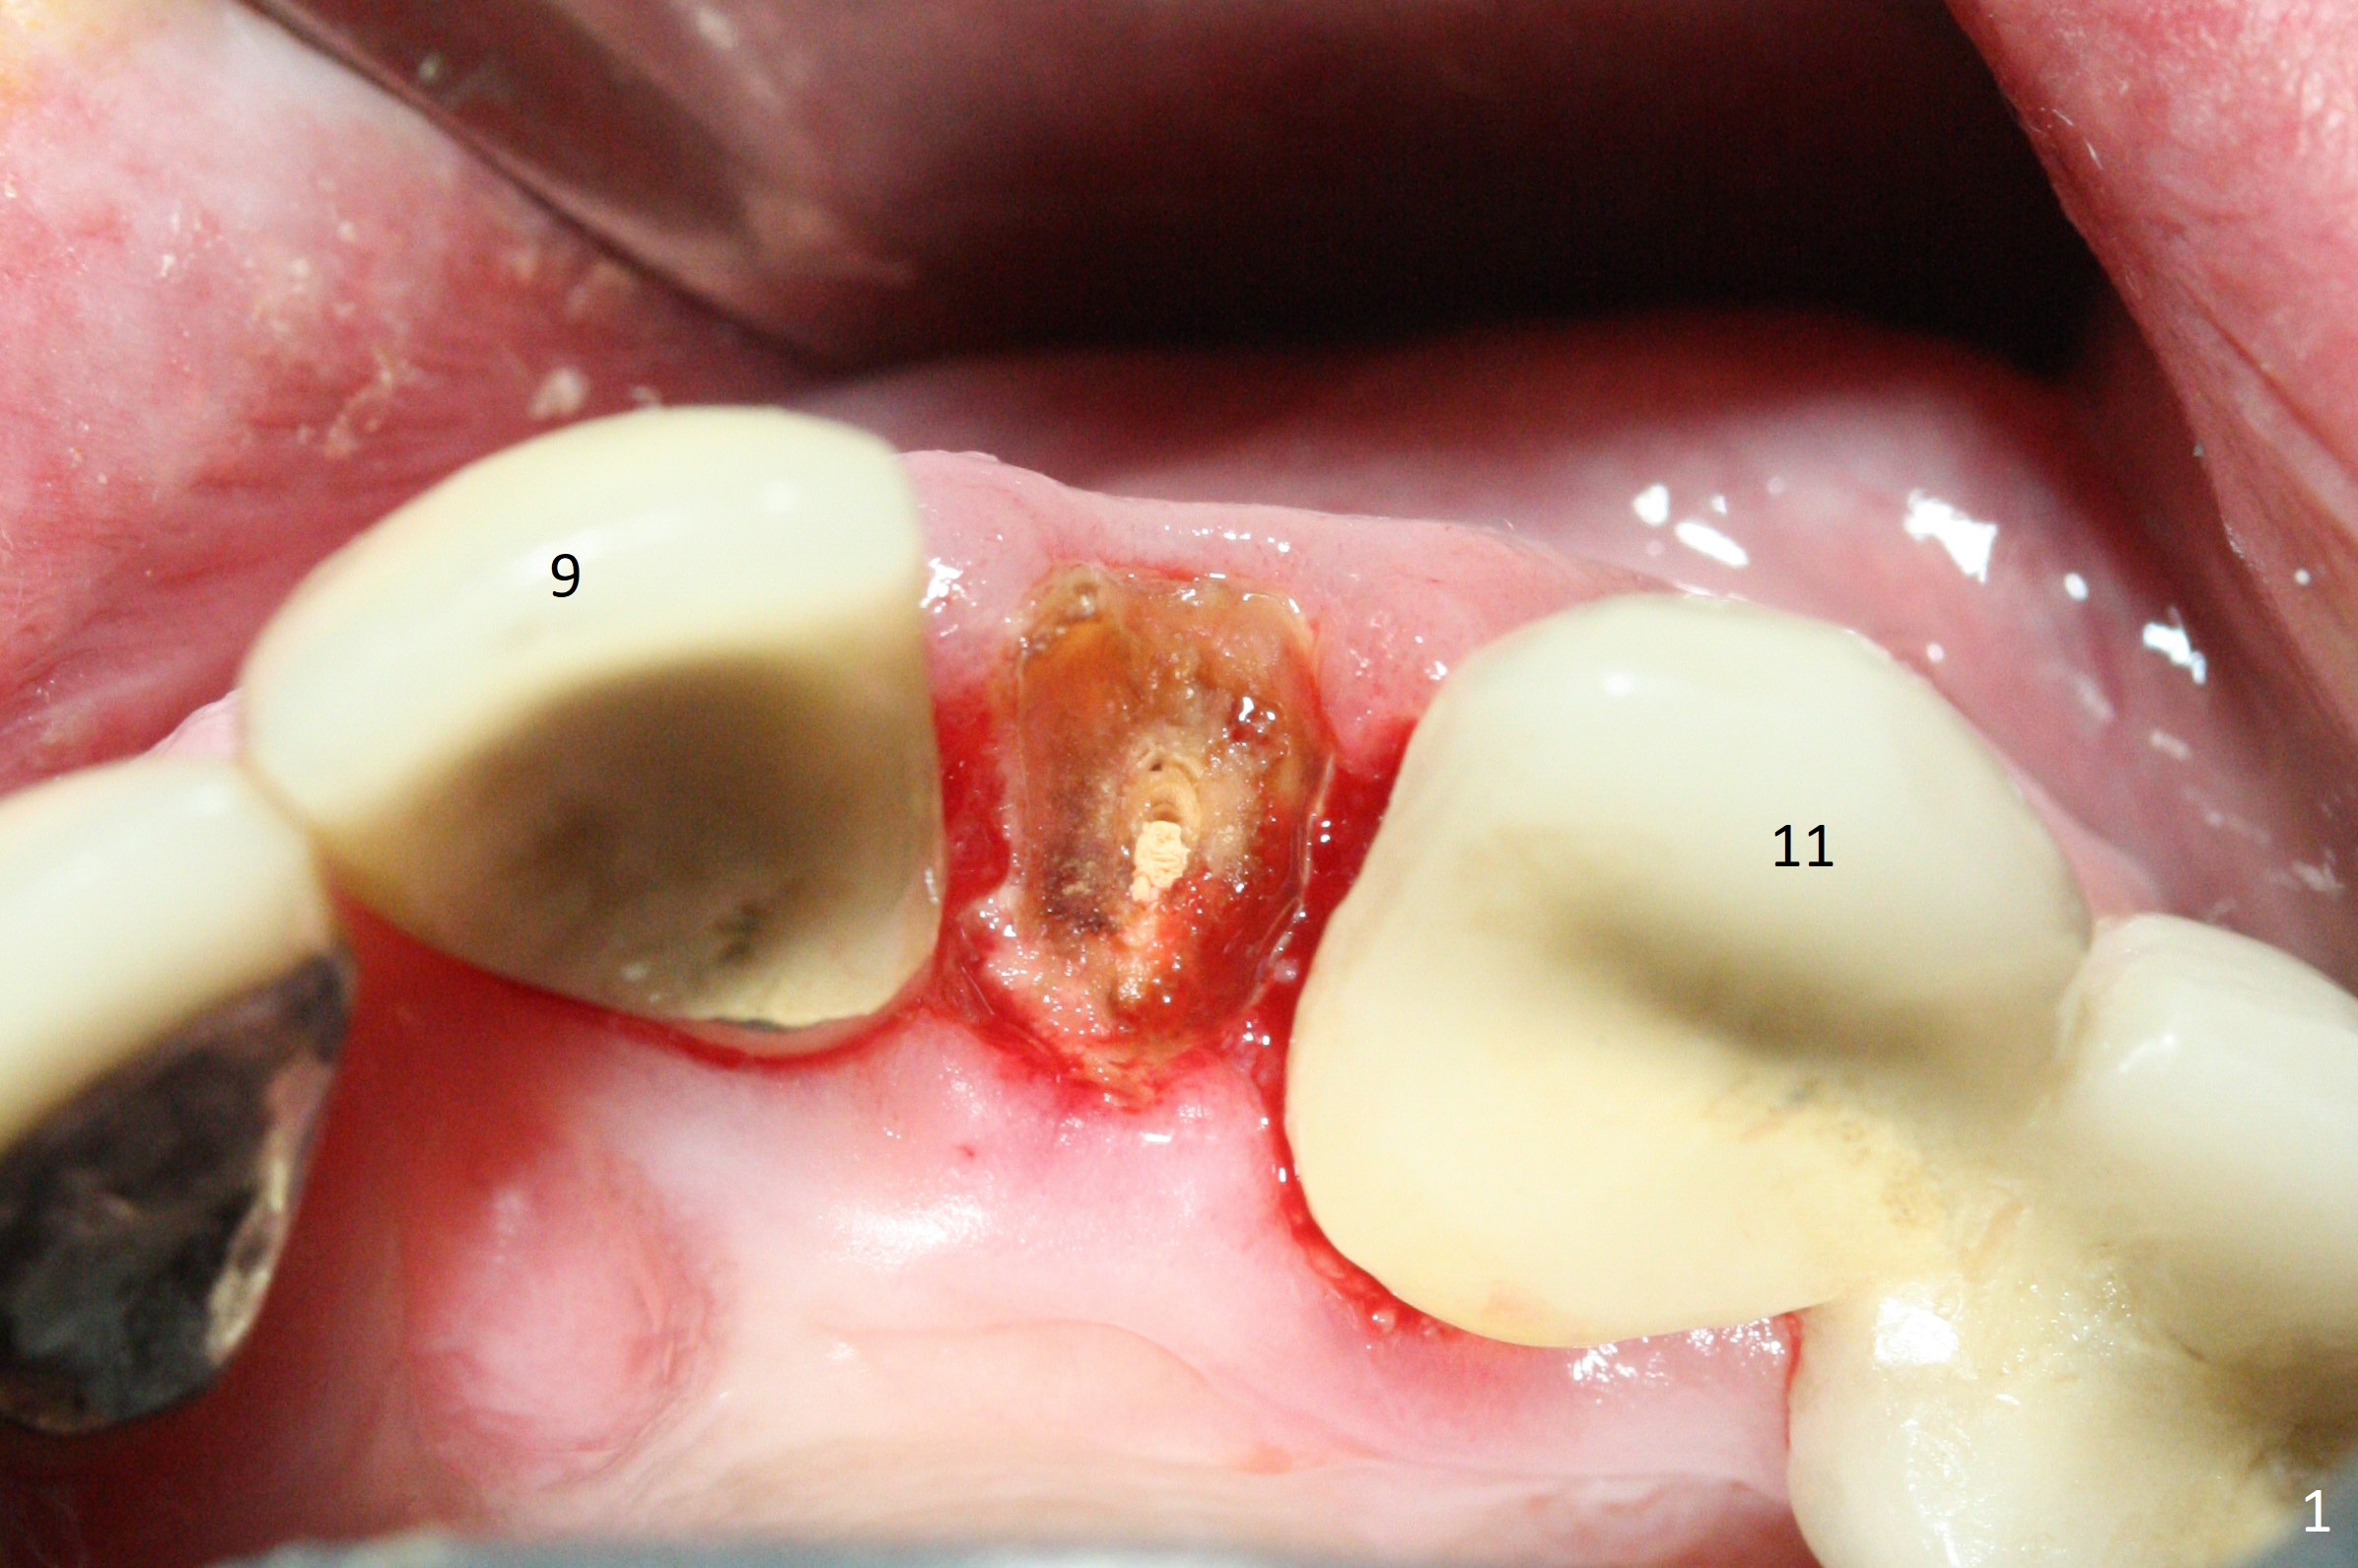

The tooth #10 fractures at the cervix, but is attached to the gingiva.  After extraction of the coronal portion of the tooth, the mesiodistal space palatally is found to be narrow (~4.7 mm, Fig.1).  It appears that a 1-piece implant is indicated because of the narrow mesiodistal space.  In fact the buccal plate of the socket is intact (Fig.2).  The initial osteotomy seems to be mesial (Fig.1) and is moved distal using Lindamann bur.  After sequential osteotomy, a 3x10 mm dummy implant is still mesial (Fig.4).  Following further distalization, a 3x14 mm implant is placed (Fig.5,6; <30 Ncm).  Vera Graft is placed in the remaining socket prior to provisional fabrication (Fig.6 *).  The socket outline disappears 7 months postop (Fig.7).  Panoramic X-ray is taken 1 year 3 month post cementation.